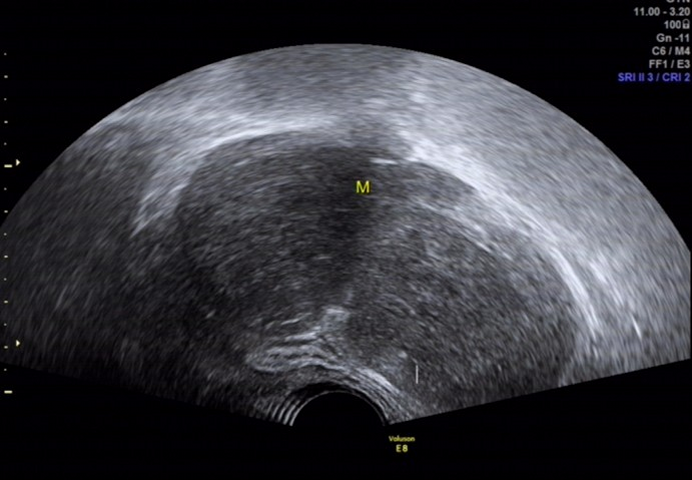

图 6 经阴道超声扫查见包块形态尚规则,与盆腔各脏器分界清楚

图 7 CDFI: 内见多个条状血流信号